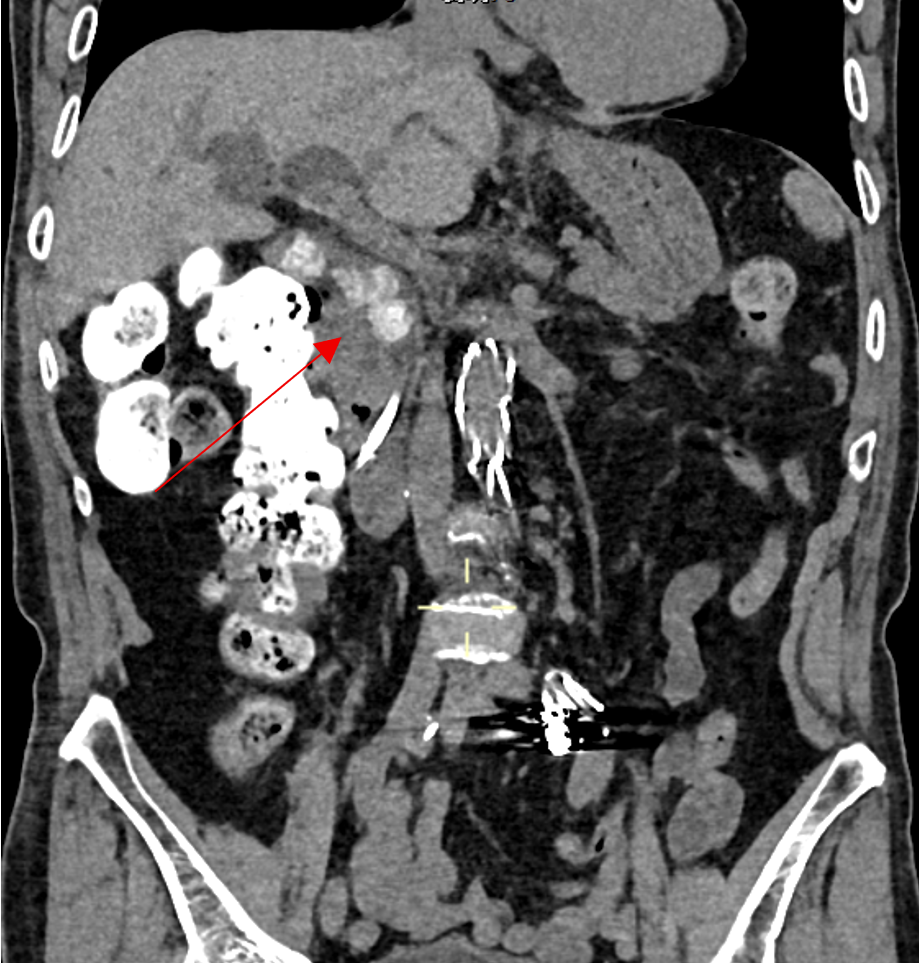

图1:CT显示胆总管内多发结石,胆总管、肝内胆管扩张明显